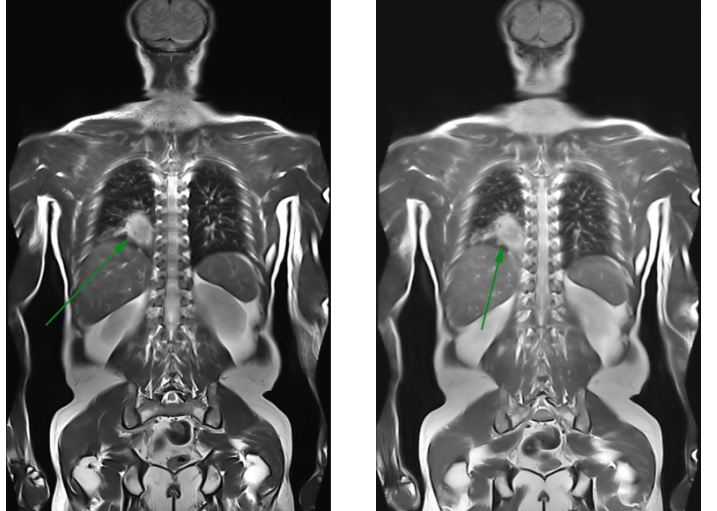

- Một số bệnh tổn thương vùng xương khớp: thoái hóa cột sống, thoát vị đĩa đệm, u tủy, u xương, nhiễm trùng khớp, các dị tật bẩm sinh...

- Người bệnh bị tổn thương các cấu trúc phần mềm như tủy sống sụn chêm, dây chằng, các sang chấn do thể thao...

- Các bệnh ung thư hoặc tầm soát ung thư (MRI toàn thân)

Kỹ thuật chụp cộng hưởng từ MRI có thể góp phần phát hiện sớm nhiều căn bệnh nguy hiểm nên được các bác sĩ chuyên gia đánh giá cao, kỹ thuật này có những ưu điểm nổi bật như:

Có khả năng đánh giá tốt tình trạng của những tổn thương rất nhỏ trong cơ thể như mạch máu, thần kinh...